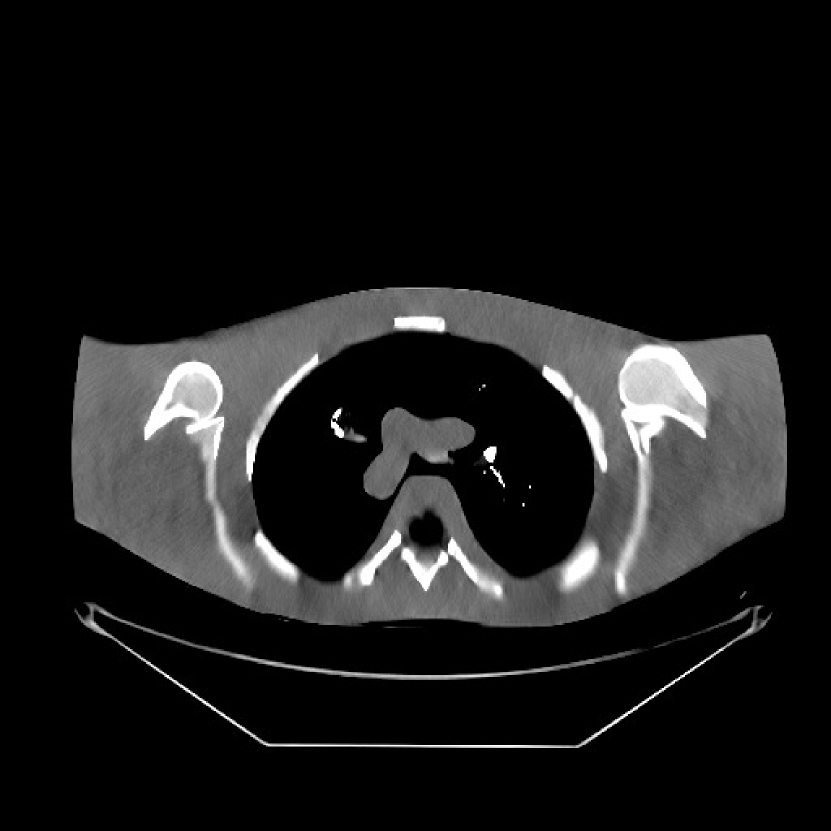

Fig. 9 shows three axial slices from the 3D reconstructions with SPULTRA and PWLS-ULTRA at : the middle slice (No. 67) and two slices located farther away from the center (No. 90 and No. 120). The image profiles along a horizontal line (shown in green) in the displayed slices are also shown in Fig. 9. The reconstructed slices using PWLS-ULTRA appear darker around the center compared to the “true” clinical image and the reconstructions with SPULTRA. This means PWLS-ULTRA produces a strong bias in the reconstruction. The bias can be observed more clearly in the profile plots: the pixel intensities for the SPULTRA reconstruction better follow those of the “true” clinical image, while those for the PWLS-ULTRA reconstruction are much worse than the “true” values. Moreover, SPULTRA achieves sharper rising and failing edges compared to PWLS-ULTRA. In other words, SPULTRA also achieves better resolution than PWLS-ULTRA. Fig. 9 also shows a zoomed-in ROI for each of the chosen slices, and highlights some small details with arrows. It is clear that in addition to reducing the bias, SPULTRA reconstructs image details better than PWLS-ULTRA.